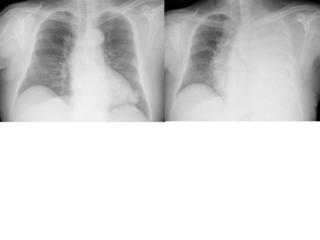

例えば肺の大きさ。

volume

lossや反対に過膨張などの所見は、圧倒的に胸部正面写真がわかりやすいですね。

C縦隔や横隔膜の動きを見る

これらの動きから、肺容量の増減がわかります。